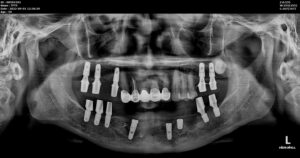

에이디중부치과에서는 양산전체임플란트 진행 시

파노라마 사진과 3D CT 촬영을 통해

아래턱 하방으로 지나가는

하치조 신경관의 위치,

위턱 잔존 치조골과 상악동 막과의 거리,

눈에 보이지 않는 해부학적 구조물 등을

면밀하게 파악한 뒤

임플란트 식립 하기 좋은 위치를 선정하였으며,

시뮬레이션을 통해

식립 될 Fixture의 두께와 길이를 선정하고

식립 될 방향까지 미리 파악하였습니다.

정밀한 사전 검사와 시뮬레이션 덕분에

구강 내에서 정확한 위치에

정확한 방향으로

안정적으로 임플란트 식립을 도와드렸습니다.

식립 마무리 후 3D CT 촬영을 통해

식립이 잘 된 것을 확인하였으며,

모든 치료가 마무리된

파노라마 사진과 구강 내 사진인데요.